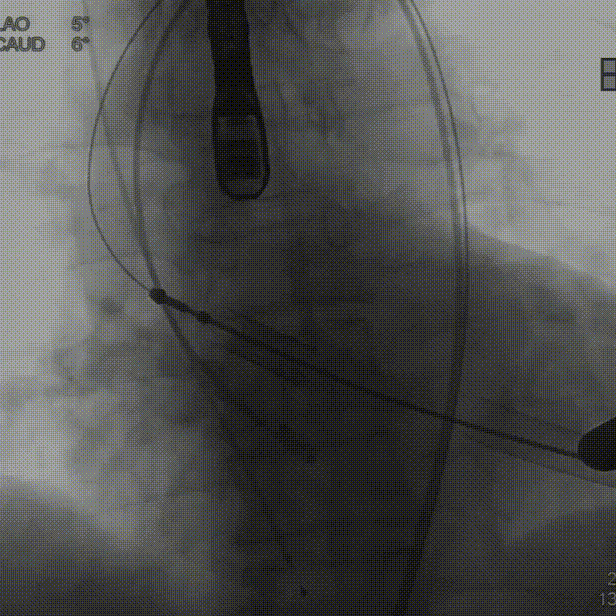

术中建议造影角度LAO 4°,CAU 6°(其它考角度如下图):

横位心,心室角度68°:

主动脉根部造影:

定位件入窦后造影: